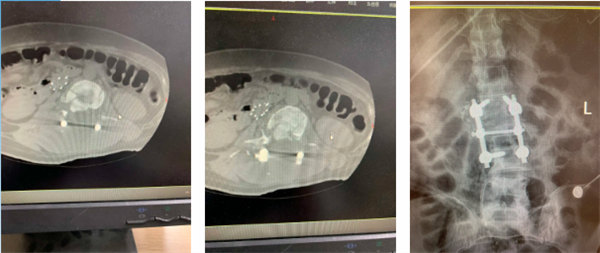

術(shù)后影像

入院后三天,手術(shù)團隊分“兩路”在全麻狀態(tài)下為患者實施了手術(shù)治療。首先由胸外科主任陳瑜團隊為患者行“左側(cè)部分肋骨骨折切口復(fù)位內(nèi)固定術(shù)+左側(cè)胸腔鏡探查術(shù)”,隨后在胸外科團隊保駕護航下,骨一科副主任王文亮團隊為患者行“腰Ⅱ椎體爆裂性骨折切開復(fù)位內(nèi)固定術(shù)+椎板切開減壓術(shù)”。在麻醉手術(shù)科、重癥醫(yī)學(xué)科、輸血科等多學(xué)科的協(xié)作配合下,手術(shù)順利完成。術(shù)后第二天,患者左下肢肌力恢復(fù)至III級,右下肢肌力I級。

后續(xù)康復(fù)過程中,骨一科醫(yī)護人員細心指導(dǎo)、耐心鼓勵,康復(fù)醫(yī)學(xué)科輔助針灸、理療等治療措施,終于在術(shù)后第3個月,患者可借助輔助器下地活動。